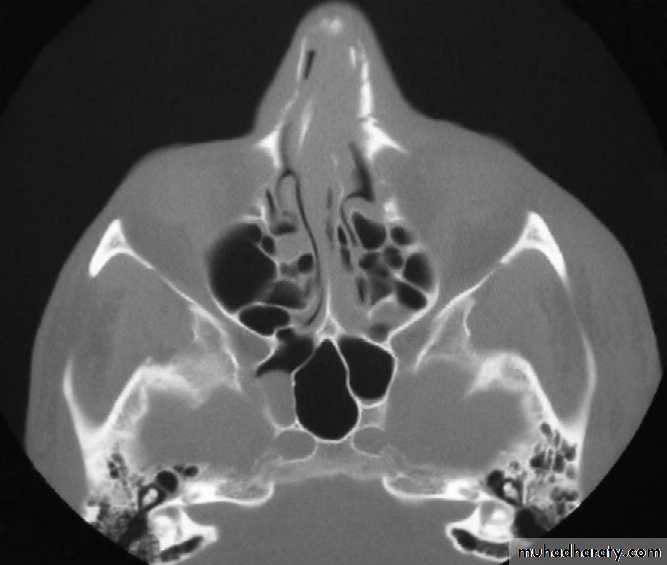

Bilateral comminuted nasal bone fractures and septal deviation following motor vehicle collision.